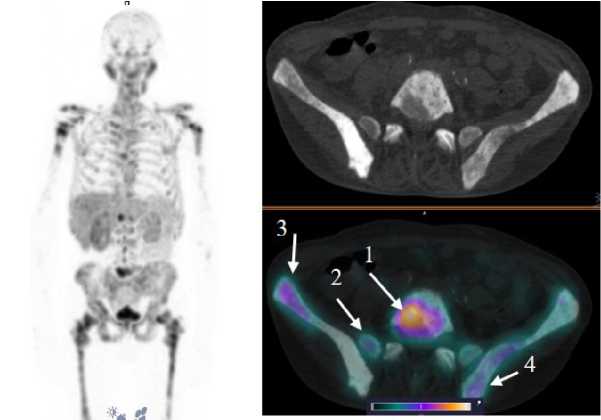

Рис. 5. MIP-реконструкция, КТ и совмещенное ОФЭКТ/КТ изображение больного раком предстательной железы с множественными метастазами в кости и лимфатические узлы малого таза через 2 ч после инъекции [99mTc]Tc-HYNIC-PSMA. На ОФЭКТ-КТ изображении стрелкой отмечено накопление РФЛП в паховом лимфатическом узле слева (1) SUVmax 22; бедренной кости слева (2) SUVmax 53; лонной кости слева (3) SUVmax 22,8

Fig. 5. MIP reconstruction, CT and SPECT/CT image of a patient with prostate cancer with multiple metastases to bones and pelvic lymph nodes 2 hours after injection of [99mTc]Tc-HYNIC-PSMA. Аccumulation of radiopharmaceutical in the pathological areas is indicated by the arrow on the SPECT-CT image: inguinal lymph node on the left (1) SUVmax 22; femur on the left (2) SUVmax 53; pubic bone on the left (3) SUVmax 22.8